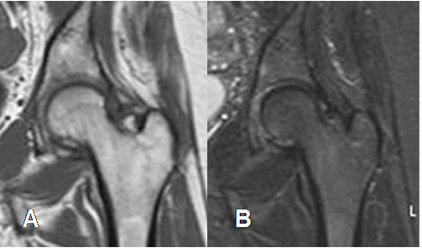

Fig 20. Osteoporosis transitoria.

A: RM coronal en T1 y B: RM coronal en STIR. El mismo paciente anterior, con estudio normal después de 4 meses.